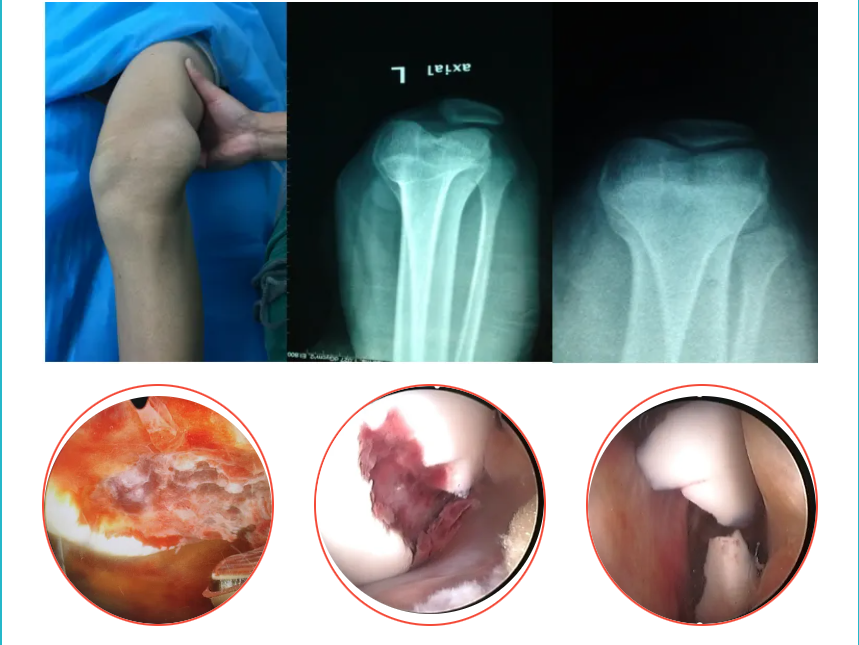

肘部畸形

肘內(nèi)翻矯正